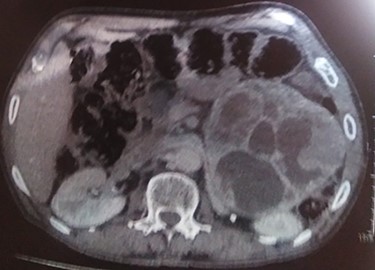

A 70-year-old patient, diabetic on insulin who presented with left flank pain evolving for 6 months. Medical history showed only the presence of headaches. The clinical examination showed a mass of the left flank, a pulse at 95 bpm and elevated blood pressure of 185/95 mmHg. Computed tomography (CT) showed a left retroperitoneal cystic mass measuring 13*11 cm on the axial plane with a large axis of 13 cm with a fleshy component and moderate enhancement. The left adrenal gland was not found (Fig. 2). Laboratory investigations were normal. A screening hormone test related to the adrenal gland, revealed elevated plasma catecholamine levels, epinephrine, 0.61 ng/mL (N: 0.00–0.10); norepinephrine, 2.88 ng/ml (N: 0.10–0.50). Furthermore, detailed 24-h urinalyses during hospitalization showed elevated urinary catecholamine levels, norepinephrine, 995.4 mg/24 h (N: 31.0–160.0), metanephrine levels with metanephrine, 2.35 mg/24 h (N: 0.04–0.18); normetanephrine, 3.75 mg/24 h (N: 0.10–0.28; Table 1). Based on these findings, the diagnosis of cystic pheochromocytoma was suspected. The patient’s blood pressure was controlled with the alpha-blocker. The patient was taken up for exploratory laparotomy. Intraoperatively, a giant cystic mass was found arising from the left adrenal gland and was adherent to the left renal pedicle and pancreas. Manipulation of the mass resulted in extreme blood pressure fluctuations. The patient underwent removal of this adrenal cystic tumor. Macroscopically, the mass measures 15 × 12 × 12 cm, round, well-circumscribed and encapsulated. It had a central cystic space filled with hemorrhagic fluid. Histologically, the tumor was confirmed as a pheochromocytoma, and no malignant foci were detected (Fig. 3). Immunohistochemical staining revealed that the tumor cells were diffusely positive for chromogranin A (Fig. 1). The patient had an uneventful recovery and was discharged on the fifth postoperative day. Three months following surgery, the patient remains stable with no tumor recurrence and his most recent ambulatory blood pressure was 114/67 mmHg with low-dose amlodipine. After 6 months of follow-up, his 24-h urine metanephrine and normetanephrine were within a normal range.